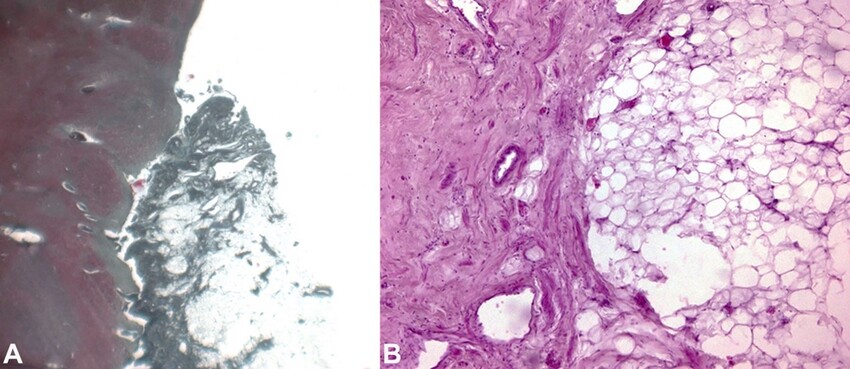

During the autopsy investigation, fragments of viscera and biological fluids were sampled for the usual chemical-toxicological analyses, as well as the brain and heart in toto and samples of the lung, liver, kidneys, and spleen for subsequent histopathological study. The latter were conducted using standard post-fixative techniques. The sections obtained were stained using basic H&E and Masson trichrome histochemical staining. Slides were observed with a Leica DMR optical microscope, capturing the most significant images with a Leica DC300F Digital Camera.

Toxicological analyses were negative for determining Blood Alcohol Concentration (BAC), narcotics, and psychotropic substances. On the other hand, histopathological investigations of the viscera and the cerebellopontine neoformation showed a formation composed by mature adipocytes, allowing to define it as an intracranial lipoma (Figure 3).

No evidence of malignancy was observed. Areas of acute neuronal hypoxic distress in the bulbar site (olive) and diffuse cerebral edema of a severe degree, mainly in the right hemisphere, were also documented (Figure 4).